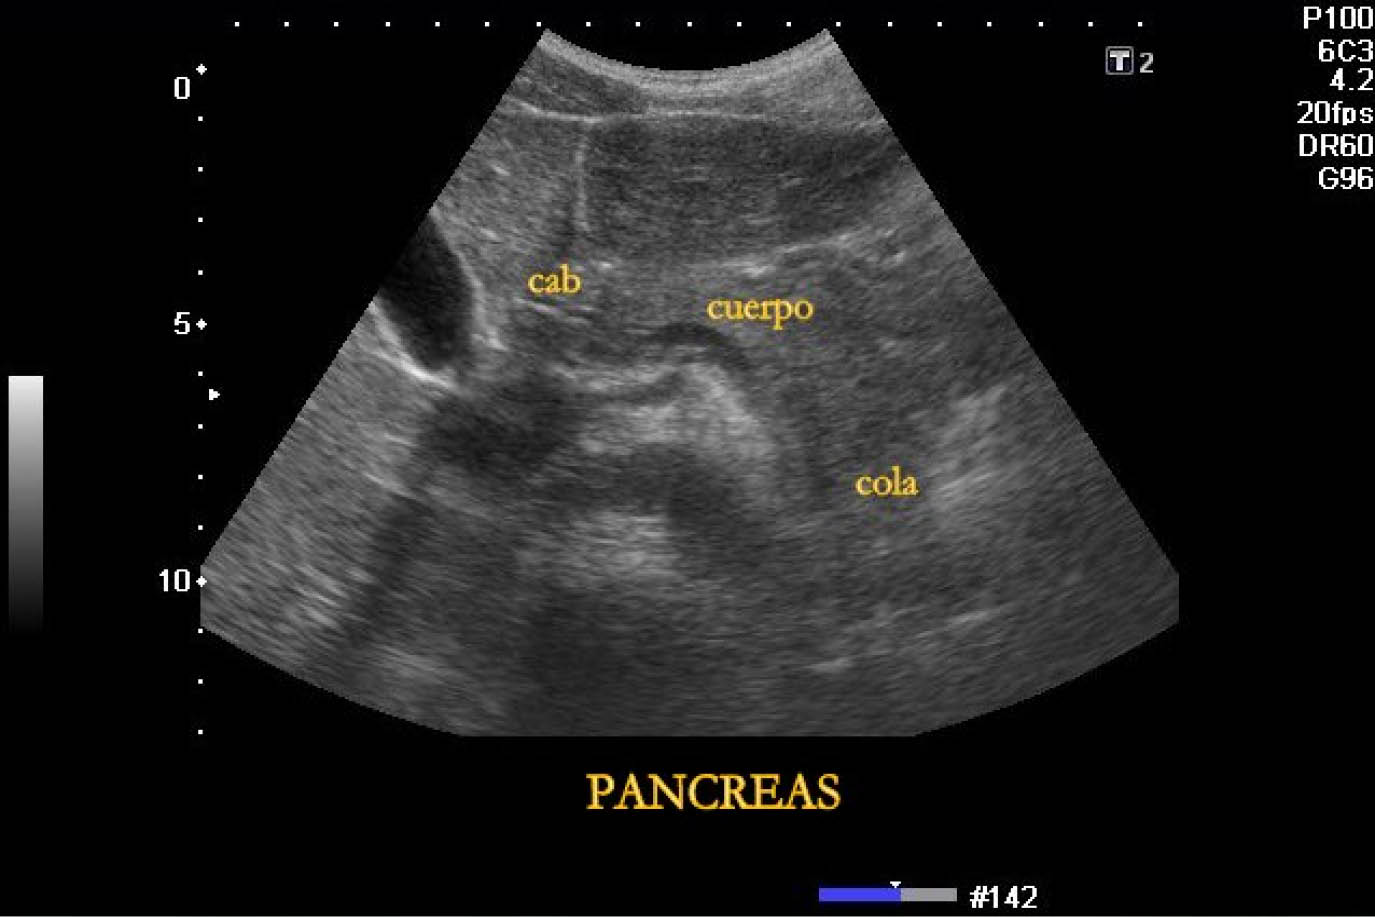

La realización de estudios ecográficos del páncreas en modo b es ampliamente utilizado a bajo costo y disponibilidad.

Los estudios de tumores pancreáticos son una nueva aplicación del ultrasonido reforzado por medio de contraste, esta técnica puede mejorar la caracterización de las lesiones pancreáticas.

Existe en la literatura cierto número de artículos que describen los patrones más comunes de las lesiones sólidas y quísticas mediante ultrasonido reforzado por contraste, aunque no han sido pocos, han sido realizados de forma mono céntrica, no reflejando la utilidad global de esta técnica en una forma de uso más extensa, por lo tanto un estudio multicentrico ha sido llevado a cabo para describir os patrones típicos mediante ultrasonido reforzado por contraste y evaluar su exactitud diagnostica en la caracterización de las más comunes lesiones pancreáticas.